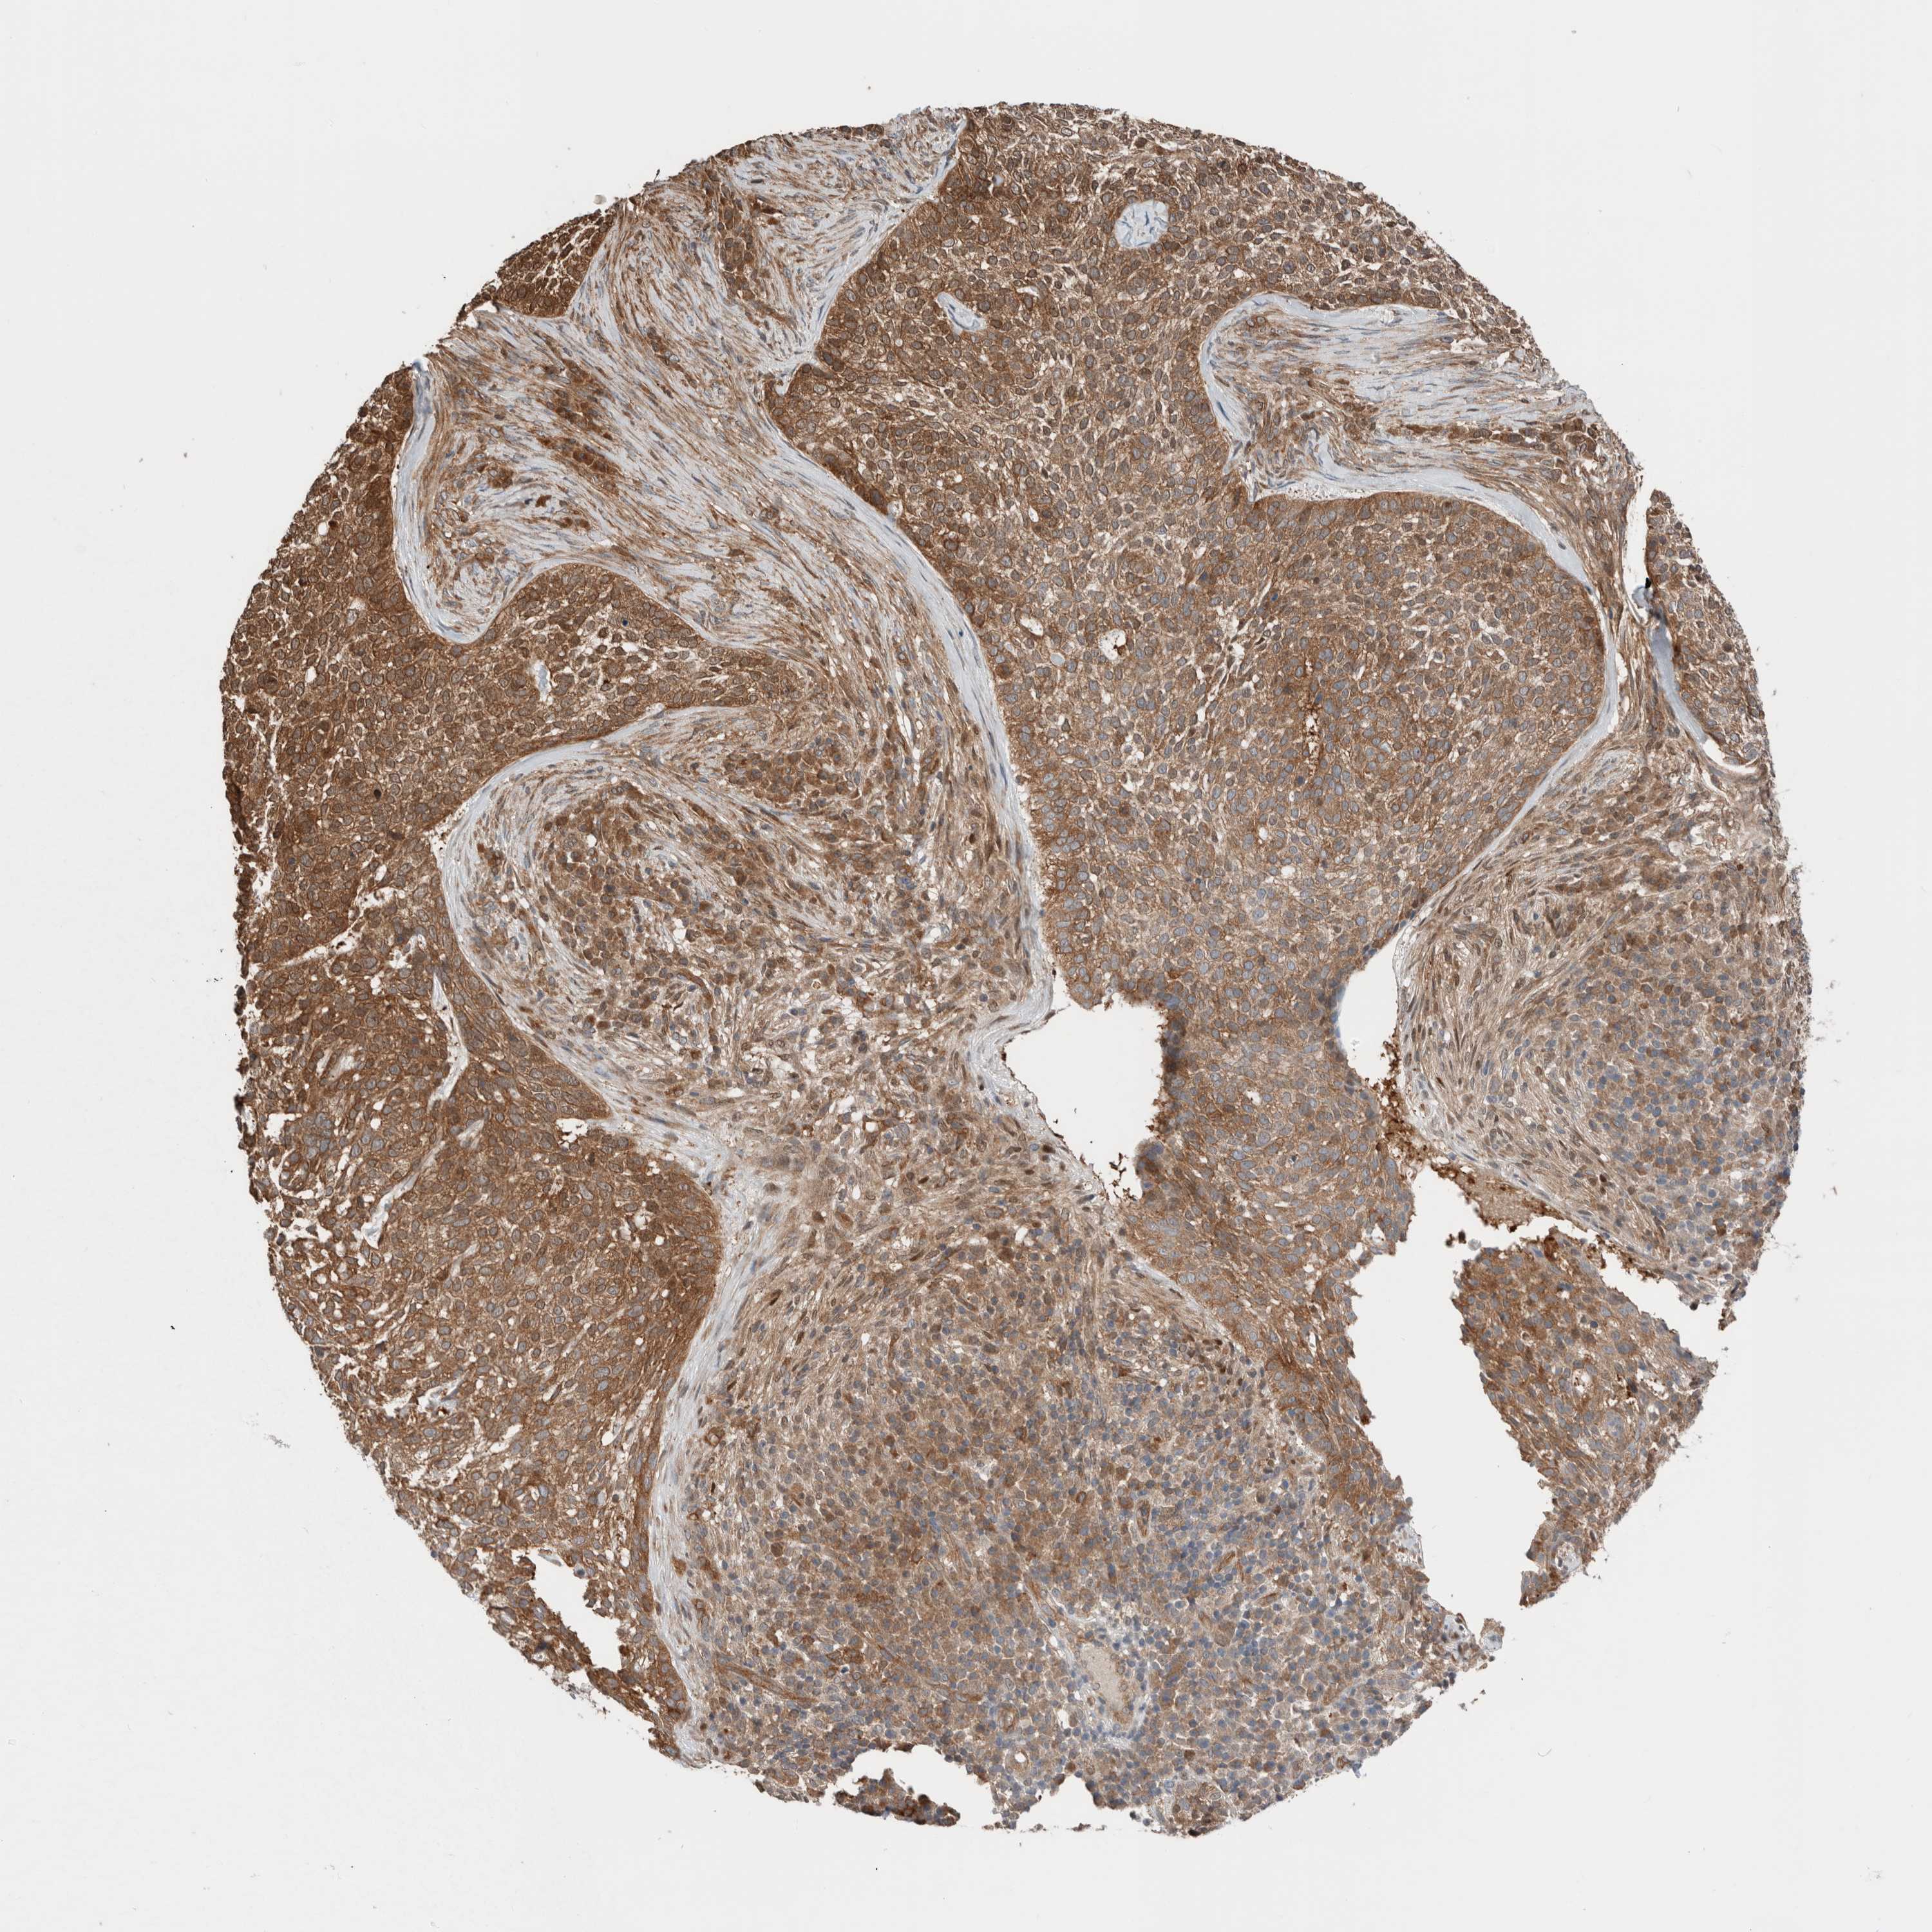

SKIN CANCER - Protein expressioni

A mouse-over function shows sample information and annotation data. Click on an image to view it in a full screen mode. Samples can be filtered based on level of antibody staining by selecting one or several of the following categories: high, medium, low and not detected. The assay and annotation is described here.

Antibody stainingi

Antibody staining in the annotated cell types in the current human tissue is reported as not detected, low, medium, or high, based on conventional immunohistochemistry profiling in selected tissues. This score is based on the combination of the staining intensity and fraction of stained cells.

Each image is clickable and will lead to virtual microscopy that enables deeper exploration of all samples and also displays staining intensity scores, fraction scores and subcellular localization as well as patient and tissue information for each sample.

HPA030419

HPA030420

HPA030422

CAB025196

CAB080286

CAB080287

Basal cell carcinoma

Squamous cell carcinoma, NOS

Squamous cell carcinoma, metastatic, NOS